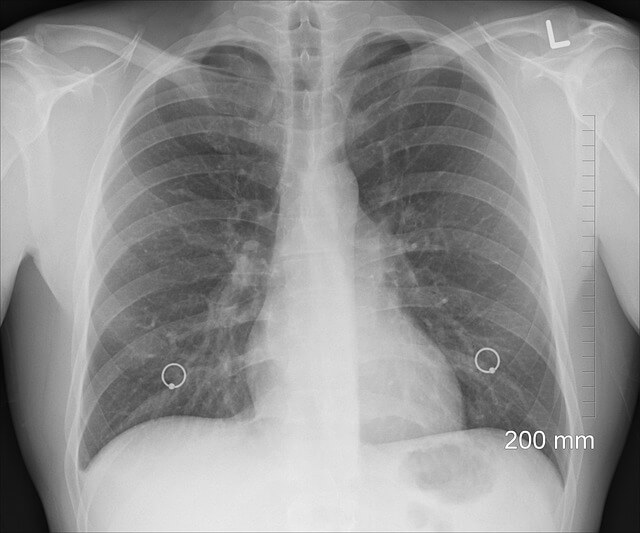

폐에 물이 차는 치료 방법

원인에 따라 치료 방법이 다르며, 대개 다음과 같은 방법이 사용됩니다.

| 치료 방법 | 설명 |

|---|---|

| 이뇨제 투여 | 체내 과잉 수분을 제거하여 폐부종을 완화 |

| 산소 치료 | 산소 공급을 통해 호흡 곤란을 완화 |

| 흉수 배액술 | 가슴에 튜브를 삽입해 흉수를 직접 배출 |